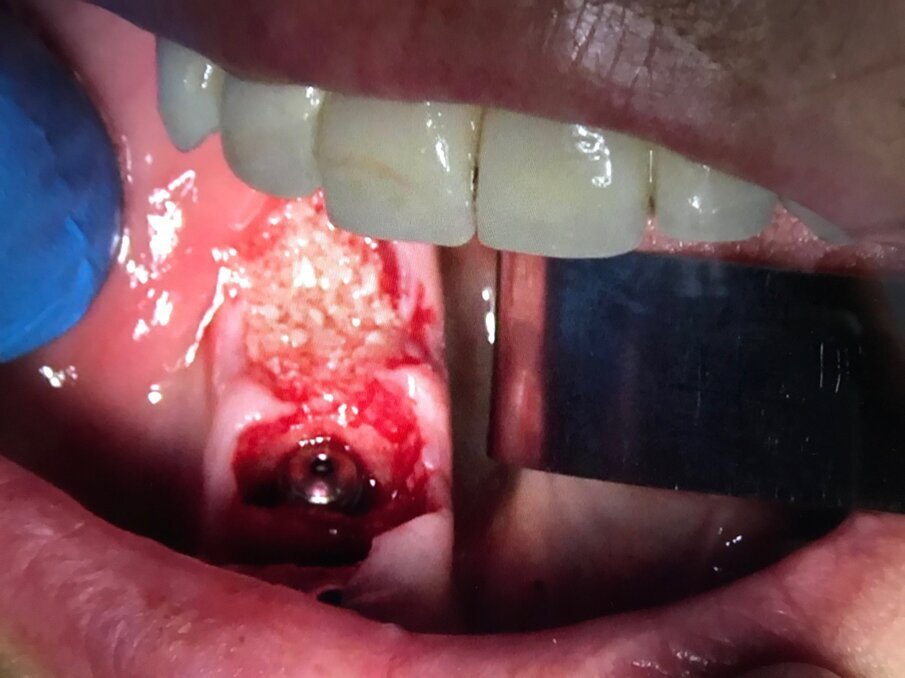

Infatti l’azione combinata su tessuti molli e su quelli duri, favorisce la rapida guarigione degli interventi chirurgici parodontali e delle tecniche additive ossee. Queste ultime devono essere predicibili, efficaci, sicure e poco costose soprattutto in relazione al fatto che tali tecniche spesso, sono finalizzate alla riabilitazione implantare e protesica delle arcate dentarie. In tal senso una tecnica che rende rapido e sicuro un ciclo riabilitativo implantoprotesico, diventa necessariamente una strategia terapeutica vincente. Diverse aziende implantari hanno sviluppato conoscenze scientifiche ed abilità commerciali in questo settore; a seguire la documentazione iconografica di una sequenza chirurgica in cui l’inserzione implantare e la rigenerazione ossea guidata sono supportate da I-PRF, utilizzato come carrier addizionato a xenoinnesti di origine bovina e da A-PRF, utilizzato come bio-membrana; quest’ultimo per proteggere impianti inseriti ed innesti anziché i tradizionali lembi muco-periosti di scorrimento affrontati e suturati tra di loro (Figg. 11-15).

Fig. 12 - Fase 2: Impianti Multysystem inseriti e filino della discrepanza alveolo-implantare con I-PRF addizionato di xenoinnesto.

Fig. 13 - Fase 3: A-PRF utilizzato come membrana di contenimento. Non è necessario elevare lembi vestibolari e linguali per accollare i margini gengivali.